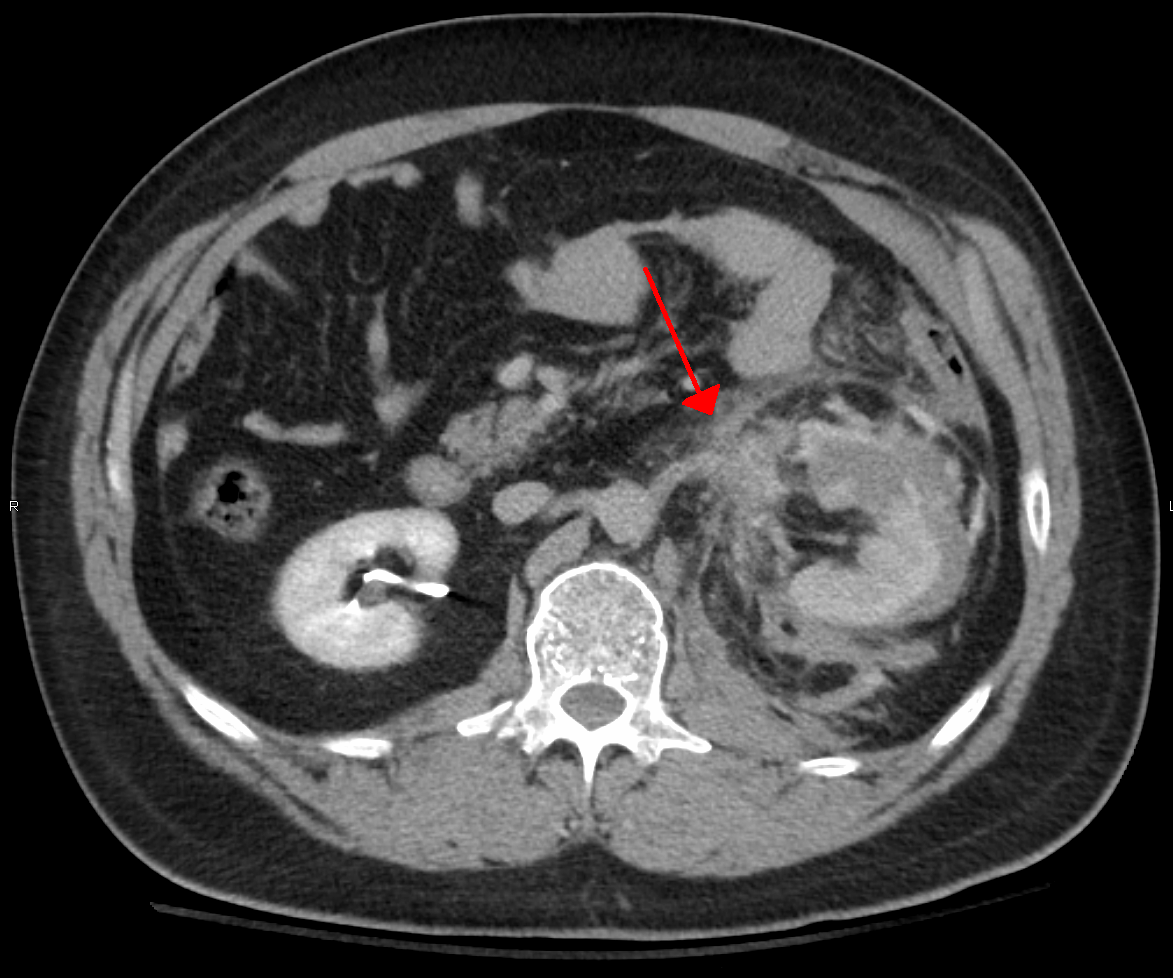

둔기 복부 외상(BAT)은 모든 둔기 외상의 75%를 차지하며, 자동차 사고가 가장 흔한 원인이다.[3][4] 자동차 사고 시 급격한 감속으로 인해 운전자가 스티어링 휠, 대시보드, 안전 벨트 등에 부딪히면서 발생할 수 있다.[5] 충격의 정도에 따라 가벼운 타박상부터 심각한 내부 장기 파열까지 다양한 손상이 나타날 수 있다. 특히, 내부 장기 파열은 초기 징후가 뚜렷하지 않아 진단이 어려울 수 있으므로, 높은 수준의 임상적 의심이 필요하다.[6]

복강 내 장기 손상은 주로 압축과 감속이라는 두 가지 물리적 기전에 의해 발생한다.[7] 압축은 직접적인 타격이나 안전벨트, 스티어링 휠과 같은 물체에 의해 복부가 눌리면서 발생하며, 속이 빈 장기를 변형시켜 내부 압력을 높이고 파열을 유발할 수 있다.[7] 감속은 복부 내 위장관과 같이 움직이는 장기가 고정된 부위에 부딪히면서 발생하며, 장간막 파열 및 혈관 손상을 일으킬 수 있다. 간의 원 인대 파열이나 신동맥 손상이 대표적인 예시이다.[7]

둔기 복부 외상으로 인한 내부 손상은 간과 지라(둔한 지라 외상 참조)에서 가장 흔하게 발생하며, 소장이 그 다음으로 흔하다.[8]

필요에 따라 X-ray, CT, 초음파(FAST) 등 영상 검사를 시행하여 내부 손상 여부를 확인한다.[8] 특히, 복부 둔기 외상의 경우 진단적 복막 세척(DPL) 또는 CT 검사를 통해 복강 내 출혈 여부를 확인하는 것이 중요하다.[34][35] CT 검사는 손상 부위를 자세히 보여주지만, 시간이 걸리고 응급 상황에서는 즉시 확인하기 어렵다는 단점이 있다.[35]